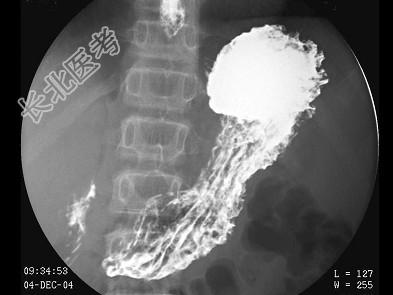

- 多项选择题男,12岁, 上腹痛1周,无规律, 无黑便史。体检:剑突下有压痛, 结合图像,最可能的诊断是 ( )

D、十二指肠溃疡